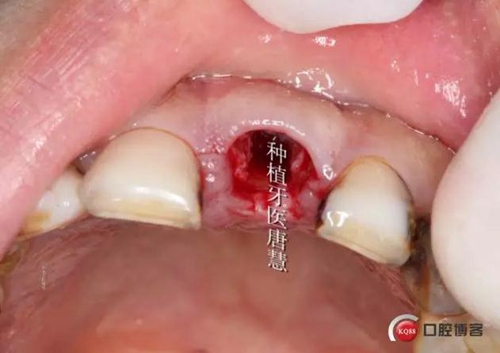

口內(nèi)情況

2.jpg